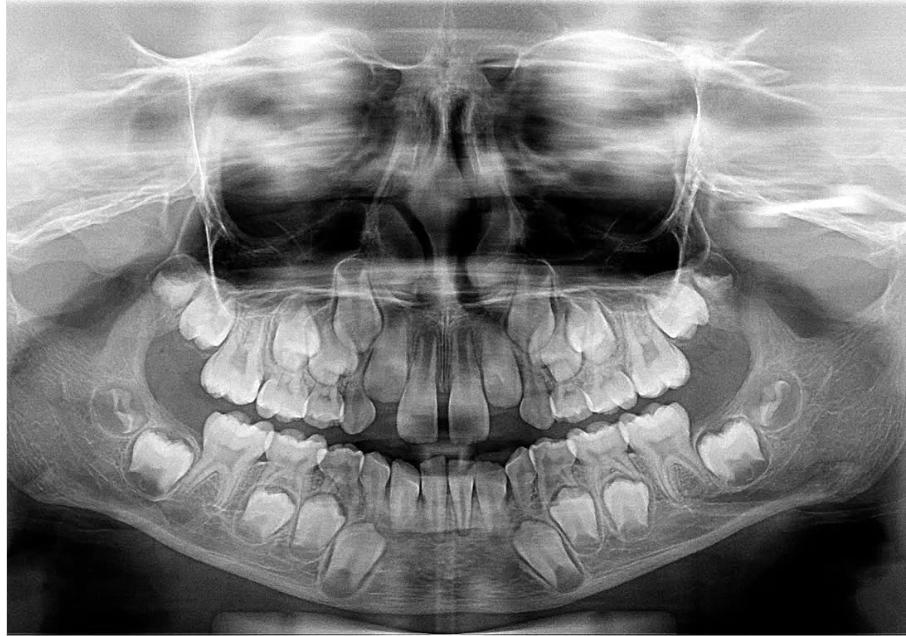

4. How old is the patient with the following X ray?